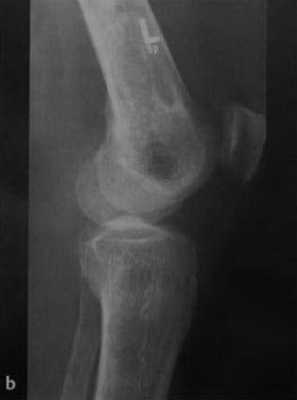

Рентгенологические признаки инфаркта кости

- В ранней стадии - остеопения и потеря трабекулярности костной ткани с окружающим склеротическим кольцом

- Участки склероза, образующиеся в зоне некроза кости, и формирование относительно новой костной ткани

- В поздней стадии - неравномерные участки затемнения или кальцинаты (изображение в виде морской гальки, гроздьев винограда, мишени или кольца), обычно расположенные на периферии

- Зона инфаркта кости может иметь длину до 20 см

- При инфаркте в области эпифиза языковидное или клиновидное затемнение распространяется от основания эпифиза на суставную поверхность.

b) Рентгенологическое исследование демонстрирует выраженный склеротический край и центральный участок снижения рентгенопрозрачности в дистальном отделе бедренной кости и в большеберцовой кости. Проксимальный отдел бедренной кости демонстрирует участок частичного грубого склероза, который иногда трудно отличить от энхондромы.